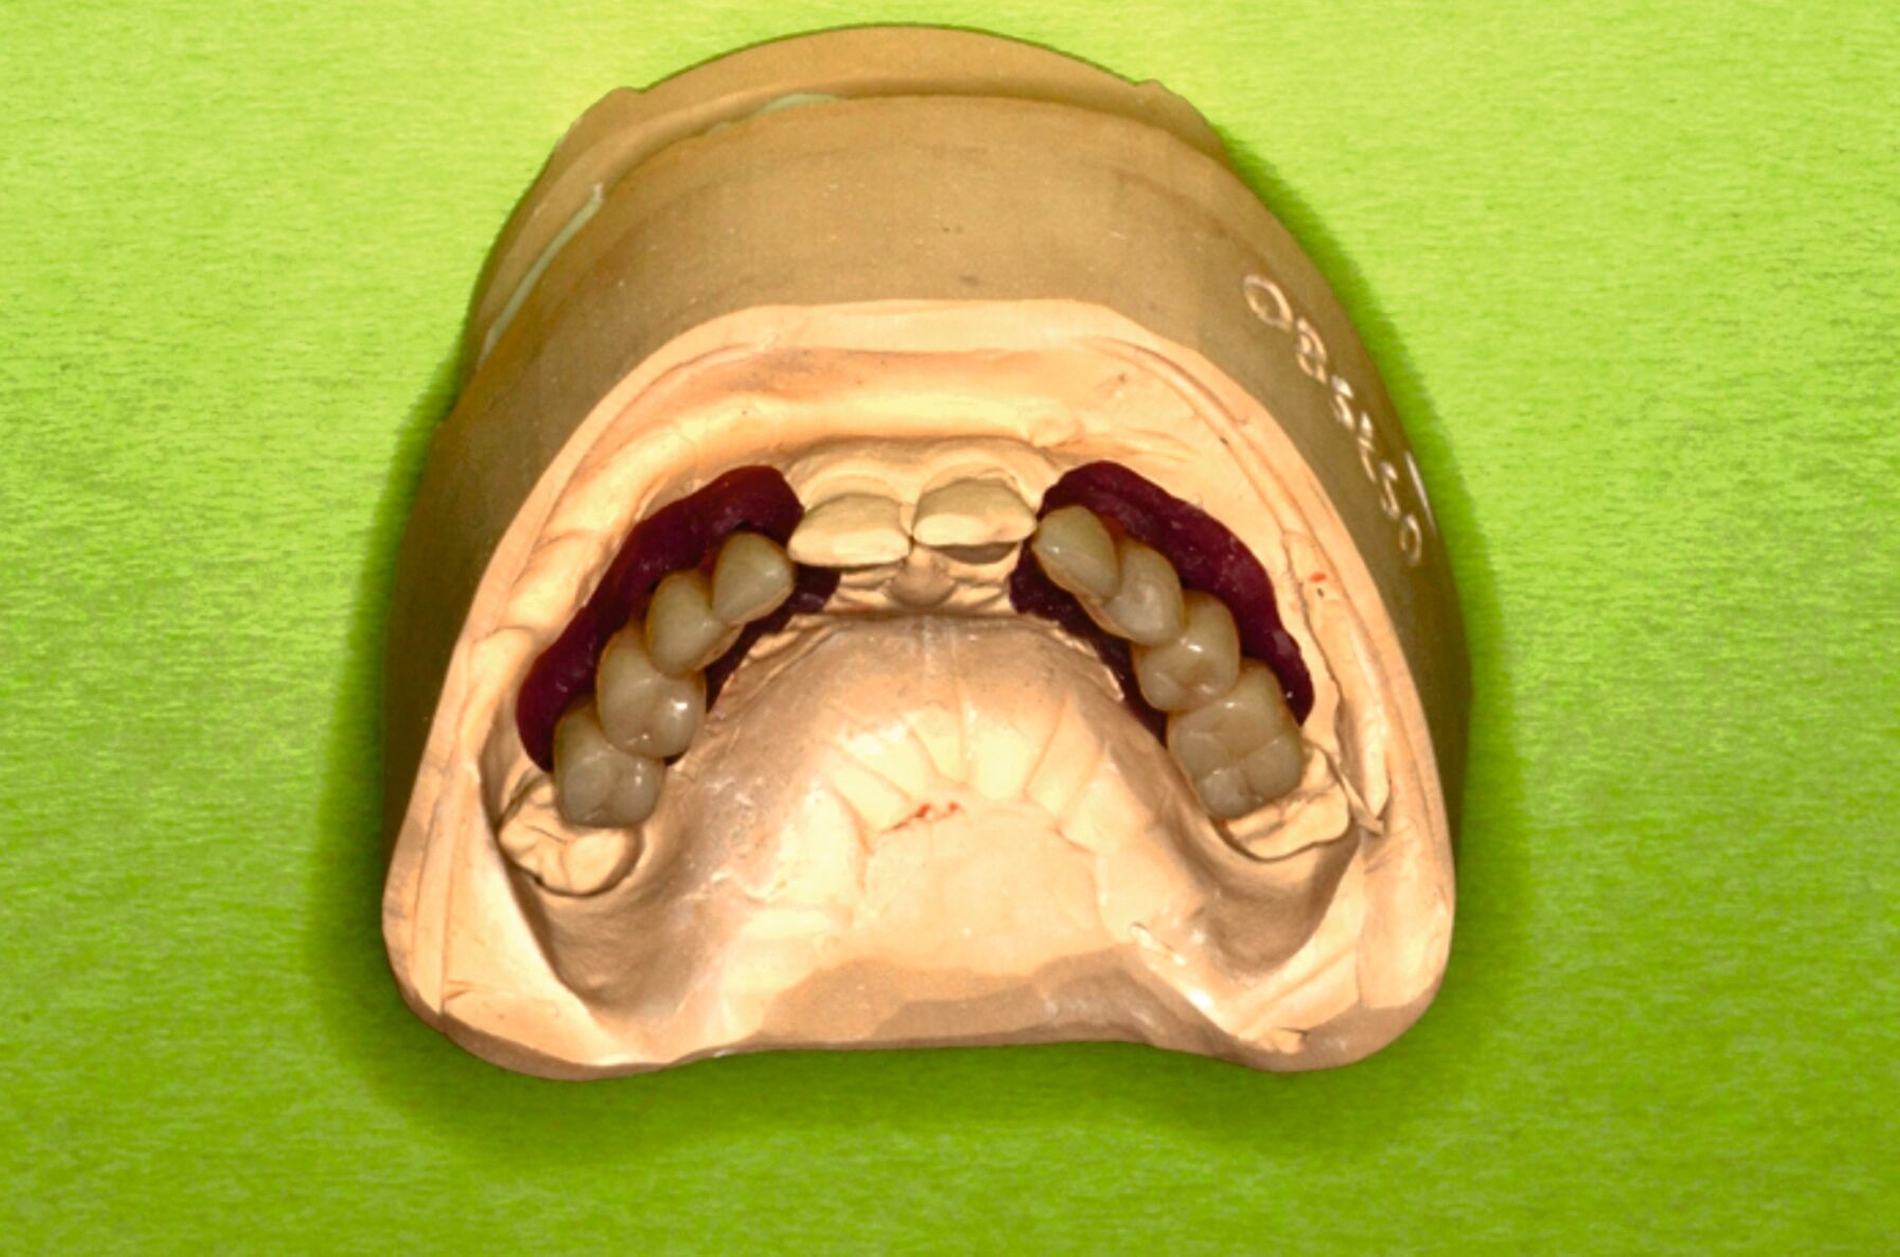

Zu Beginn der Behandlungsplanung wurden ein digitales OPG sowie Planungsmodelle erstellt (Abbildung 2). Interdisziplinär wurden mit dem Prothetiker, Chirurgen und Zahntechniker anhand der vorliegenden Modellanalysen und der klinischen Situation des Patienten verschiedene Therapieoptionen entwickelt und gemeinsam bewertet.

Eine mögliche und indizierte Umstellungsosteotomie wurde vom Patienten abgelehnt. Da seitens des Patienten eine Kopfbissstellung möglich war, wurde eine Bissumstellung und -hebung mit nur noch geringgradigem Vorbiss und anschließender Zahnimplantation in Erwägung gezogen. Begonnen wurde mit einer temporären Schienentherapie zur Neuorientierung der Bisslage (Abbildung 3). Da der Patient die angepasste Bisshebung tolerierte, wurde diese nach Entfernung der persistierenden Milchzähne 55, 53, 52, 62 und 83 temporär mittels einer Valplastprothese (Abbildung 4) als Interimsersatz im Oberkiefer gesichert.